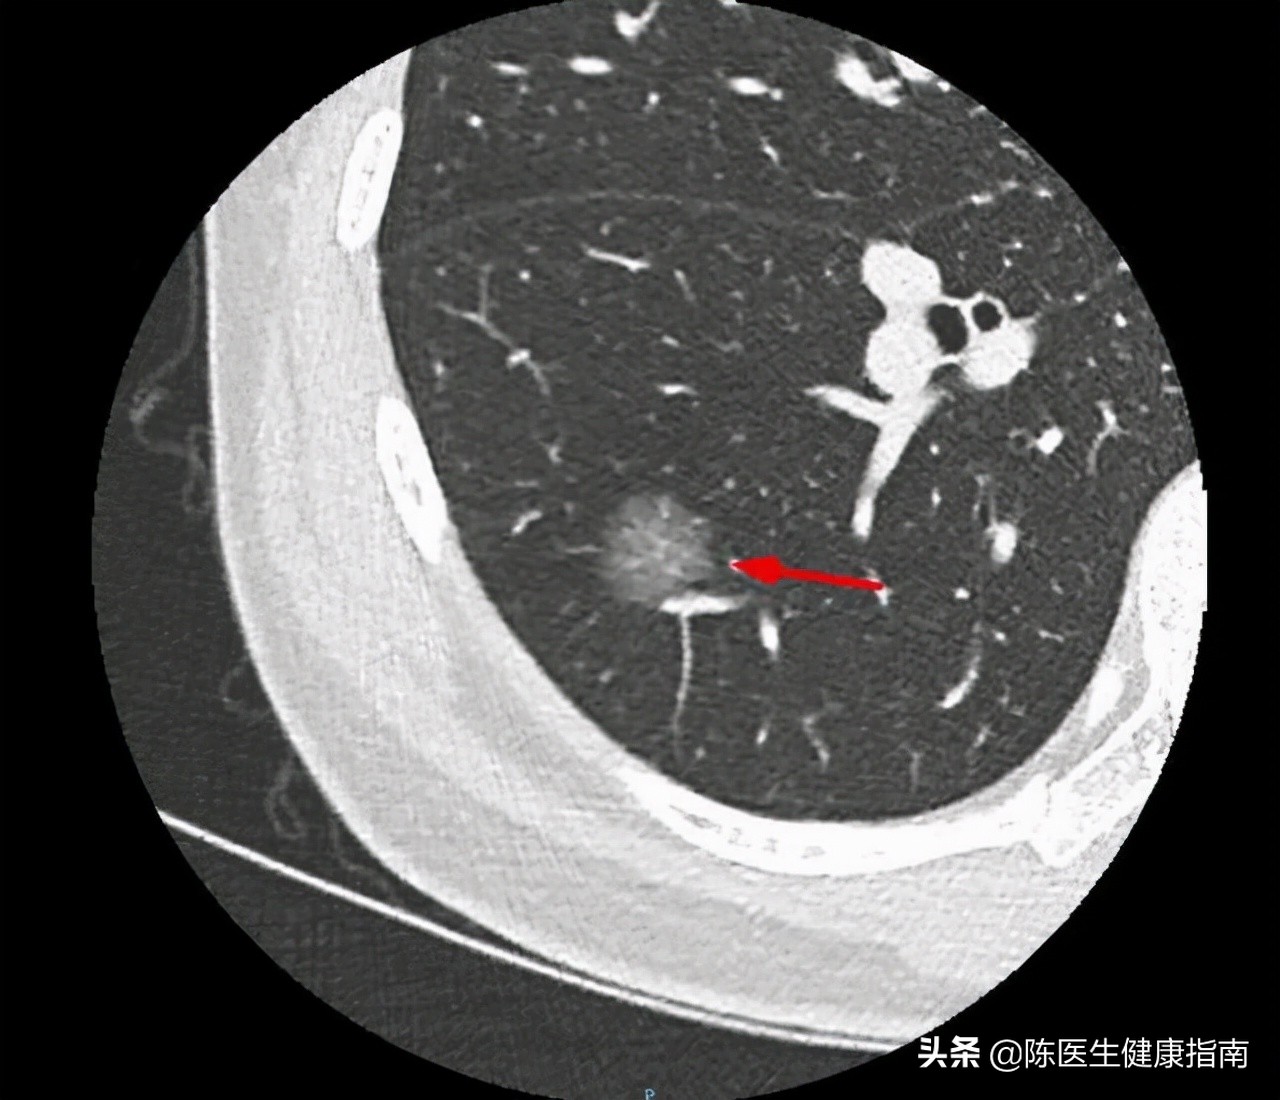

锐利的石棉纤维进入肺间质,激活人体的免疫系统,引起巨噬细胞聚集,即表现为肺间质炎症;机体同样会产生蛋白纤维,层层包裹石棉粉尘,以避免新伤口的产生。这些机体因“自我保护”而产生的反应,引起 肺部广泛的纤维化 ,严重者影响肺泡的气体交换功能,产生胸腔积液,患者出现 发热、呼吸困难、胸背疼痛等症状 。

石棉致癌的潜伏期通常在十年以上,经过长时间的积累,胸膜、腹膜因为长期纤维化而变厚,细胞也因为不断的损伤和修复,积累了足够的癌变倾向,最终发展为弥漫性胸膜恶性间皮瘤。